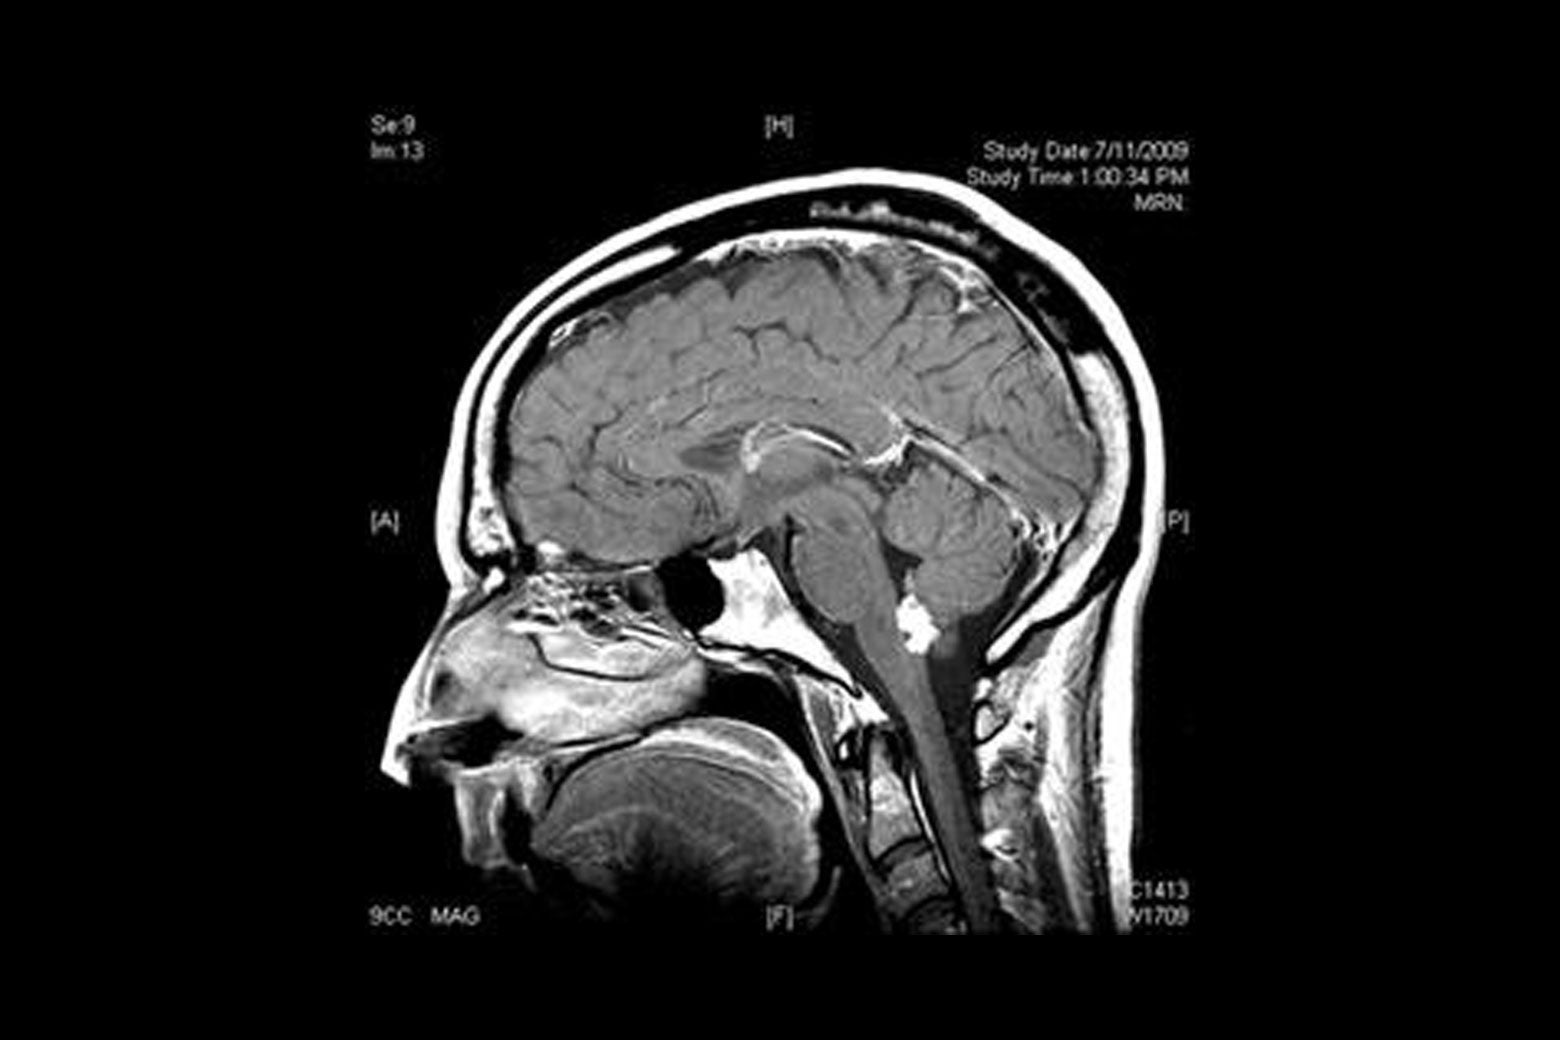

Tend to be more males than females, old. Primary brain tumors seen in dogs and cats include meningioma, glioma, choroid plexus papilloma, pituitary adenoma or adenocarcinoma, and others. I want everyone that might be going threw some of the same thing to have hope in your. Meningioma are the most common intracranial neoplasm in cats, with a frequency of around 60% of all brain tumours. Brain tumors occur more often in men than women. Examples of glial cell tumours. Brain stem tumors are heterogeneous. Tumors that form in the tissues and cells of a child's brain are called primary brain tumors. Tumors that start in the brain are called primary brain tumors. Tend to be more males than females, old. The symptoms of brain stem tumors vary greatly and can include ataxia, cranial nerve palsy, headaches, problems with speech and swallowing, hearing loss, weakness, hemiparesis. Predilections for brain tumours in dogs and cats. Stem cells in brain tumors. After taking a medical history, the doctor will examine the cat thoroughly. Brain stem glioma is usually for a focal brain stem glioma, a biopsy and removing the tumor with surgery may be considered. The brain stem, located deep in the back of the brain, is made up of the midbrain, pons, and medulla. Computed tomography (ct or cat) scan. My cat had a brain tumor. Brain tumor symptoms include headaches, nausea or vomiting, balance and walking problems, mood and personality changes, memory problems, and the most common type of primary brain tumors in children are medulloblastoma, grade i or ii astrocytoma, (or glioma) ependymoma, and brain stem. The most common indication of a brain tumor in cats is seizures, especially seizures that begin to occur after the cat has reached at least five years of age. The incidence and prevalence of spontaneous intracranial neoplasia in cats is unknown but it is commonly accepted that they are less common than dogs. Trust me he didn't pass from that it was because he got out of the house and never came back. Brain tumors in children typically come from different tissues than those affecting adults. Many brain tumors can be difficult to detect without proper testing and can display similar symptoms to ear infections or other conditions. Primary brain tumors include tumors that originate from the tissues of the brain or the brain's immediate surroundings. The brain stem is also the source of the nerves that control movement of and sensation to the face, the eyes, the throat, larynx and tongue, and the. I started some cbd for him and it helped. However, many of the times such a tumor is noticed, various treatments can be used in order to solve the problem permanently. While brain tumors in cats remain fairly uncommon, it is an issue that occurs, and that can sometimes be treated effectively. A brain tumor describes a cancerous mass within the cavity of the skull associated with the brain. Doctors diagnose brain tumors in about 85,000 people in the u.s.